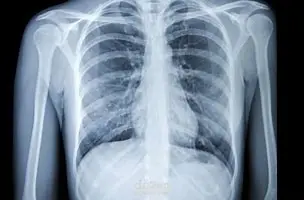

التعرف على ال (Pneumonia) -مرض رئوي- من خلال صور الاشعة التعرف على ال (Pneumonia) -مرض رئوي- من خلال صور الاشعة التعرف على ال (Pneumonia) -مرض رئوي- من خلال صور الاشعة التعرف على ال (Pneumonia) -مرض رئوي- من خلال صور الاشعة

في هذا المشروع قمت بتصميم وتدريب شبكة عصبية تلافيفية (CNN) مخصصة لاكتشاف الإصابة بالتهاب الرئة من صور الأشعة الصدرية (Chest X-Rays). بلغت دقة عاليّة (Precision تصل إلى 95٪) في تمييز الحالات الإيجابية بدقة من بين الصور المتاحة. خطوات المشروع تشمل: استيراد وتجهيز بيانات الصور (تأمين التوازن، تقسيم بيانات التدريب والاختبار). بناء بنية مخصصة لشبكة CNN، تشمل طبقات تلافيفية، تجميع (Pooling)، التطبيع (Batch Normalization) وطبقات تسلسلية نهائية. تدريب النموذج، ضبط المعاملات (hyperparameters) لتحسين الأداء. تقييم النموذج باستخدام مقاييس مثل Precision، Recall، Accuracy وغيرها. تحليل النتائج وإظهار الصور التي تم التصنيف فيها بدقة أو أخطأ النموذج لتوضيح نقاط القوة والضعف. الهدف العام للمشروع: تقديم نموذج قوي ودقيق يمكن استخدامه للمساعدة في التشخيص المبكر للحالات المحتملة من الالتهاب الرئوي، مما يسهم في تحسين السرعة والدقة في عملية الفحص الطبي.